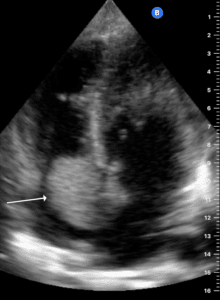

Point-of-care ultrasound (POCUS), which is routinely performed at our clinics as an extension of our physical examination [2], detected a 6 cm long segment of hypoechoic irregular circumscribed colon wall thickening around the hyperechoic pattern of bowel lumen (Pseudokidney sign) [1] in the right upper quadrant, which suggested the presence of a colon carcinoma in the ascending colon (Figure 1).

Figure 1. Ascending colon carcinoma. Probe place at right hypochondrium, probe marker pointing to patient’s head. Hypoechoic irregular circumscribed wall thickening (11.8mm) around the hyperechoic pattern of bowel lumen presenting with a kidney-shaped appearance by sonography. There is also loss of echo-stratification and compressibility.